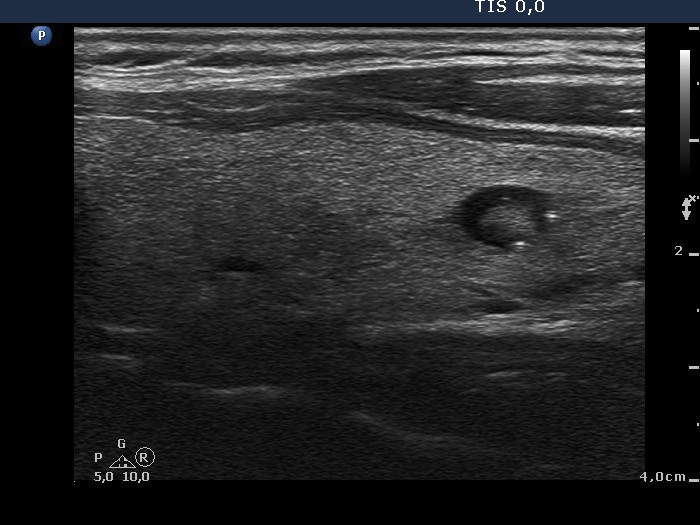

Left lobe, longitudinal view. There is a small cystic lesion having comet-tail artifacts.